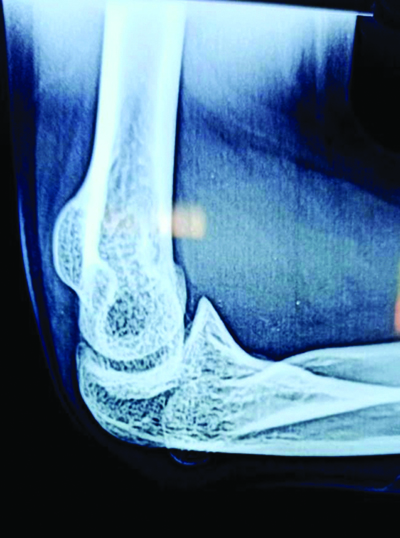

A thorough general examination of the patient revealed that the nails of both upper and lower limbs [Table/Fig-1,2] were deformed. Similar nail deformities were present in her mother and younger sister since birth, but they did not suffer from any major depressive symptoms like her. The patient also had musculoskeletal problems, like instability of her left knee since childhood and clicking in the knee while climbing stairs. The left elbow joint [Table/Fig-3] was also deformed owing to radial head subluxation.

Left-sided radial head subluxation.

Digital X-ray of right elbow showing radial head subluxation.